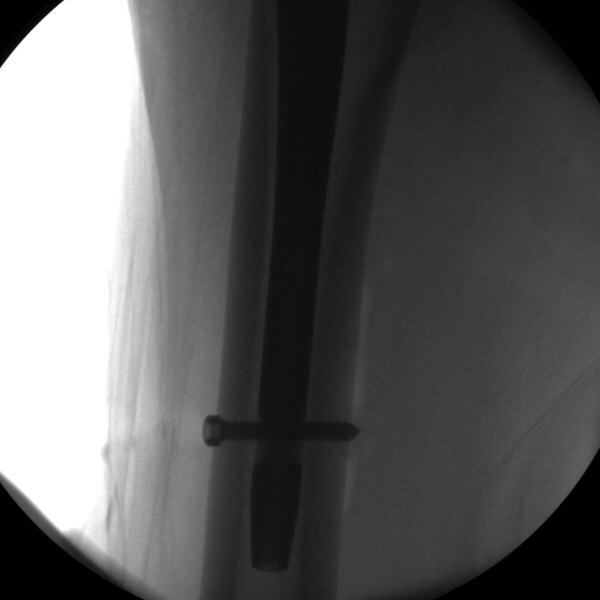

- Ändra "Target Sleeve" för distal låsskruv, oftast används statisk placering, om man önskar komprimera frakturen så kan man välja dynamisk. För in guiden, markera var den träffar huden, gör ett snitt där.

- För in låsskruvsguiden ända in till benet, tryck hårt så den går igenom fascian, lås fast genom att skruva på "Target Sleeve Knob", borra i genomlysning, tryck först mycket försiktigt mot första kortex så borret gör ett märke i kortex, sedan kan man trycka hårdare. Borra igenom båda kortex, borren ska inte träffa spiken.

- Mät med mätsticka hur lång skruv som behövs, avrunda uppåt.

- Skruva in låsskruven, kontrollera läget med genomlysning, den ska gå genom båda kortex.